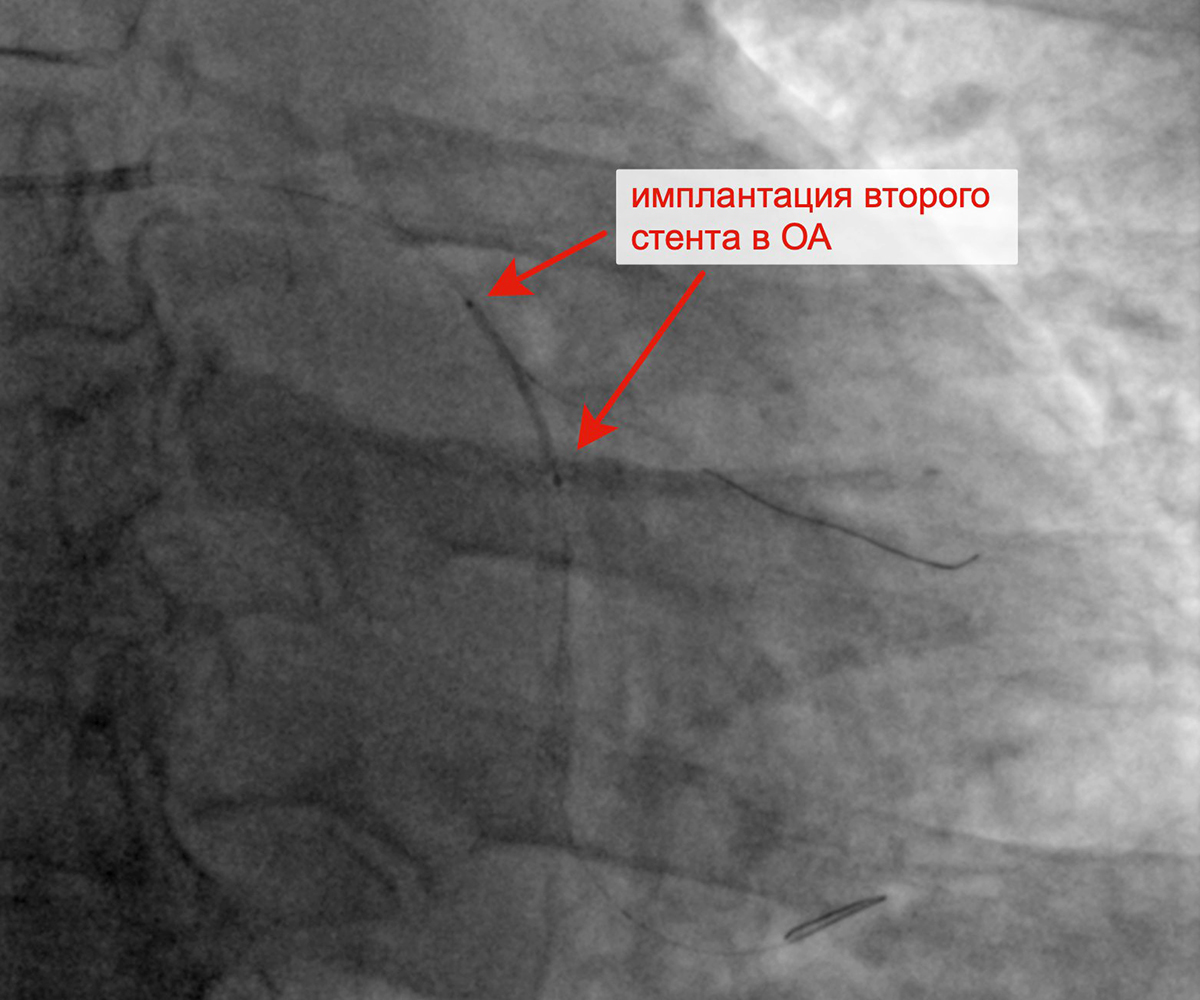

В марте 2023 г. в связи сохраняющейся одышкой, загрудинными болями при физической нагрузке пациент госпитализирован в кардиологическое отделение для решения вопроса о проведении следующего, третьего этапа реваскуляризации. Учитывая наличие ангинозных болей, результаты проведенных обследований (положительным стрессЭХО), коронарографии, наличие гемодинамически значимых стенозов коронарных артерий, принято решение о проведении баллонной ангиопластики и стентирования огибающей артерии (2 стента с лекарственным покрытием). Контрольная ангиография после успешного чрескожного коронарного вмешательства: стенты и ОА с ветвями проходимы, позиционирование стентов адекватное, диссекции или остаточного стеноза в стентированном сегменте ОА нет, кровоток TIMI 3 по ОА и всем ветвям.

Критические стенозы ОА Заведены проводники в ОА и ВТК

Имплантация первого стента в ОА Имплантация второго стента в ОА

Финальный результат имплантации 2 стентов в ОА